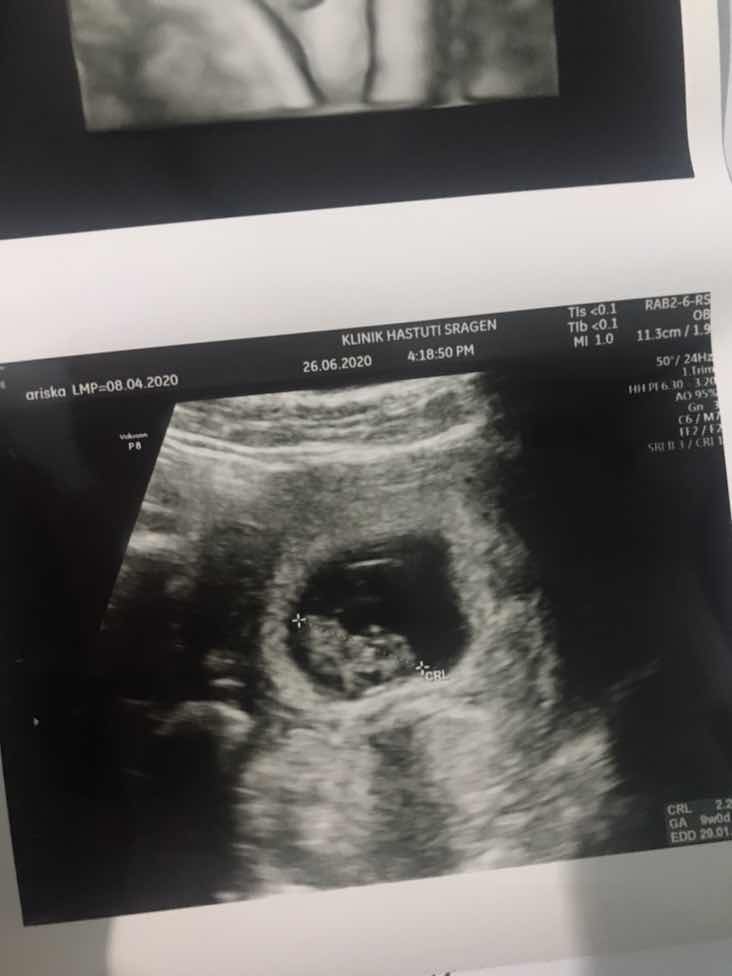

Alhamdulillah setelah usg kemaren ternyata dedeknya udah kelihatan usianya ternyata baru 9w menurut hpht udah 12w, minta doanya ya bunda bunda semoga dedeknya sehat selamat normal sampe persalinan juga lancar. Semoga doa baik kembali ke bunda bunda semuanya Aamiinn Tetap semangat